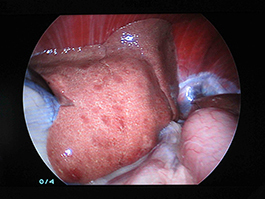

上の写真のようにトロッカーを挿入しカメラを挿入すると、右のように肝臓は瀰漫性に変色していました。 もうひとつトロッカーを挿入し、バイオプシー鉗子にて採材しました。 また肝硬変の可能性があったため、経脾的門脈造影も行ない、Cアームにて確認、異常がないことも確認致しました。

この子は『軽度肝硬変』と診断され、適切な内科療法により、元気に過ごしています。